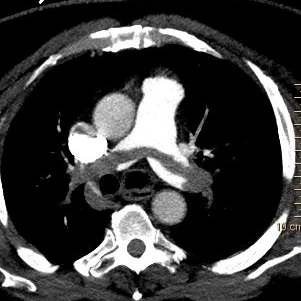

Conventional CT shows saddle embolus.